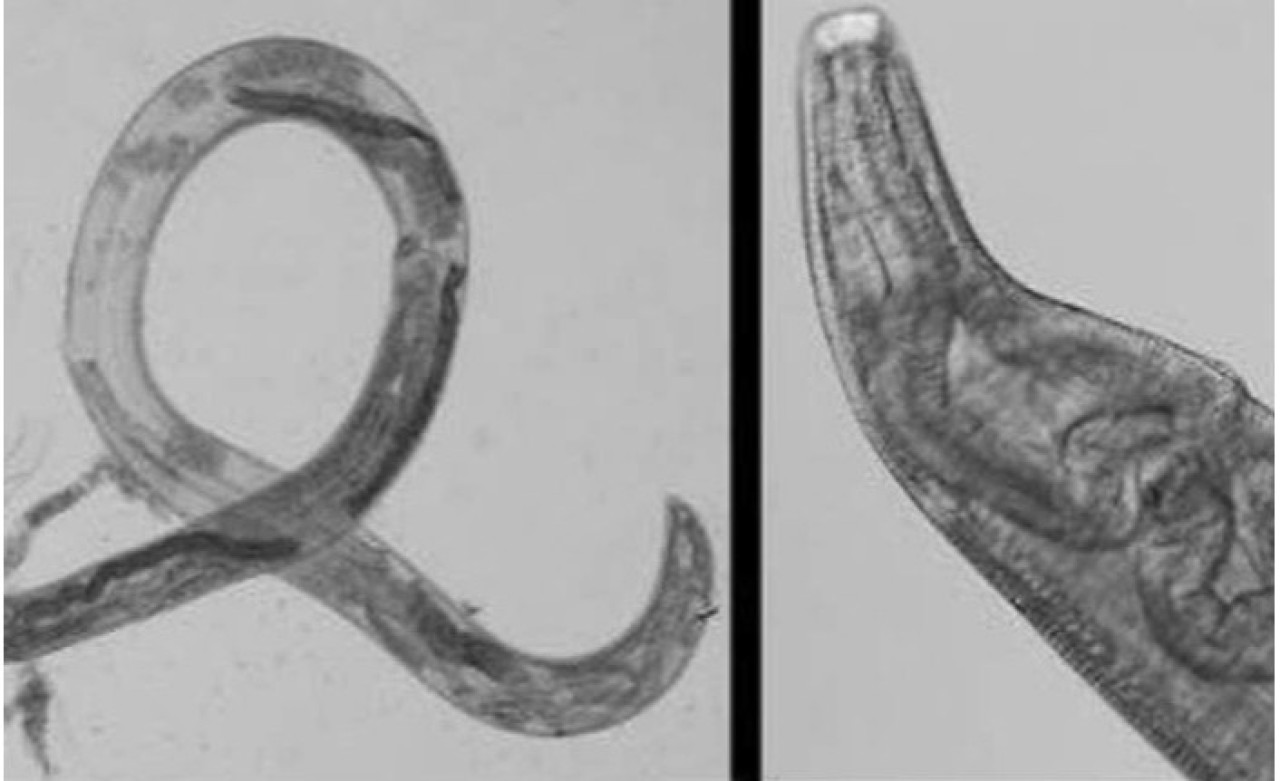

Araştırmacıların örneği analiz etmesinin sonucunda gözündeki şeyin Thelazia gulosa adı verilen bir solucan türü olduğu belirlendi. Kadına antibiyotik merhem yazılmasına rağmen her iki gözde de tahriş sorunu devam etti. Başka bir doktora giden kadının gözünden dördüncü solucan da çıkarıldı, ardından tedaviye başlandı. Bu parazitlerin tipik olarak sığırlarda bulunduğu ve belirli sinek türleri tarafından taşındığı belirtiliyor.